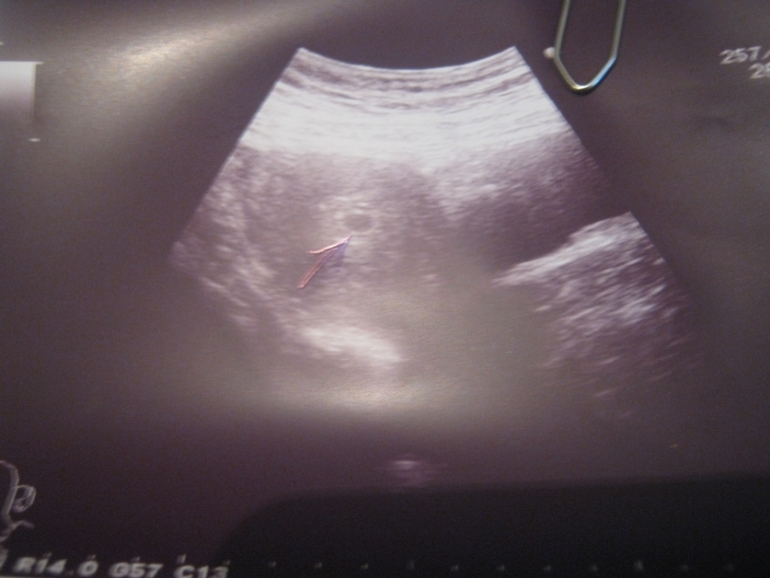

Результаты: УЗИ, КТГ, доплера, скринингаНу вот после полосатого тестика,я побежала на узи)Нас увидели,мы всего 0,8см

Но мы есть.срок 3-4 недели от зачатия и 5-6 акушерских!И вот фото на память